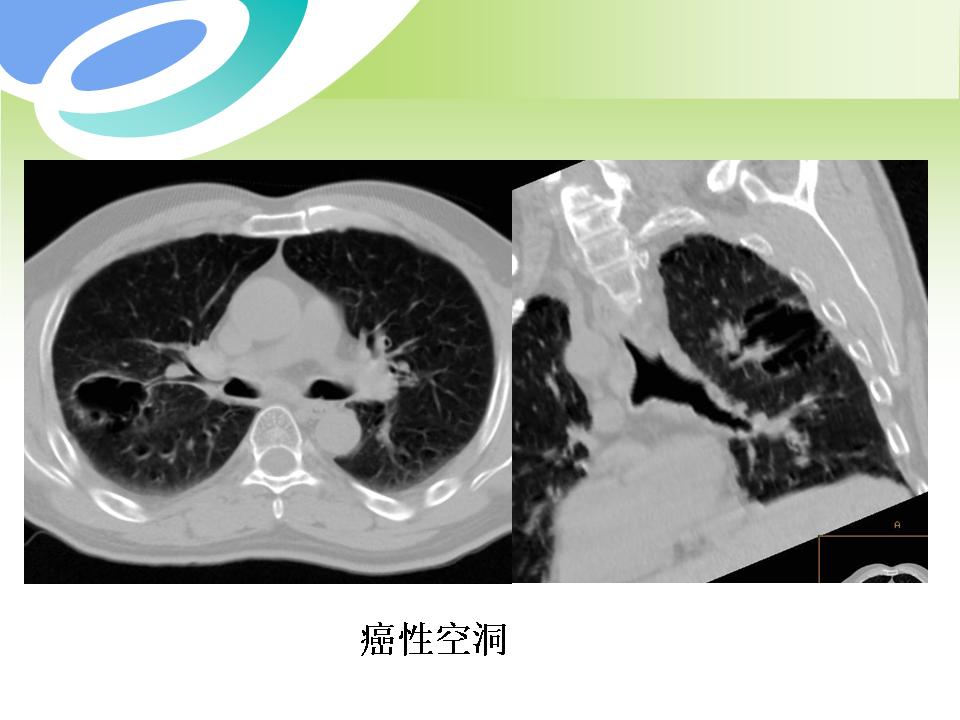

肺部病变的CT基本征象